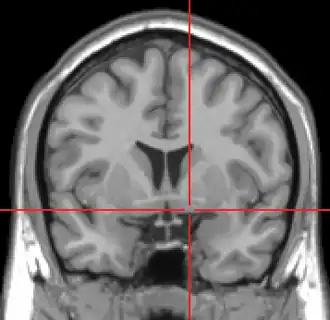

Corte coronal de IRM que muestra la ubicación de la sustancia innominada con la cruz roja. | ||